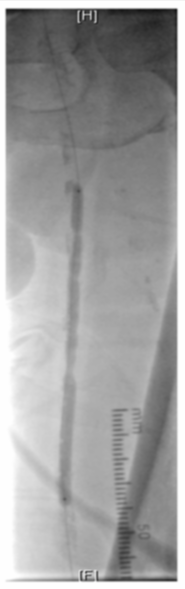

图为:导丝通过病变 置入保护伞 使用Turbohawk定向旋切

图为:股总动脉珊瑚礁病变定向旋切结果股浅动脉段尚未完成定向旋切

图为:血管准备:股浅旋切后球囊全程节段逐级式扩张

图为:评估血管准备:闭塞段残余狭窄90% ELUVIA全覆盖该区域病变

图为:股腘动脉DAART+区域性DES 最终造影